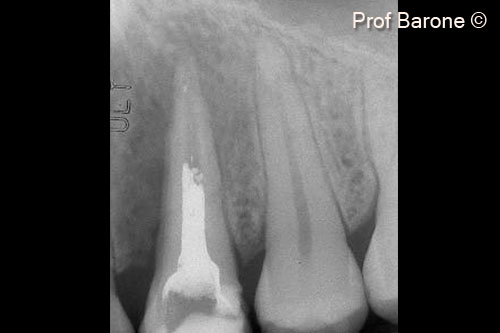

Tình hình ban đầu

Một bệnh nhân nữ (27 tuổi) có biểu hiện nhiễm trùng cấp tính và mủ từ lỗ rò ở miệng.